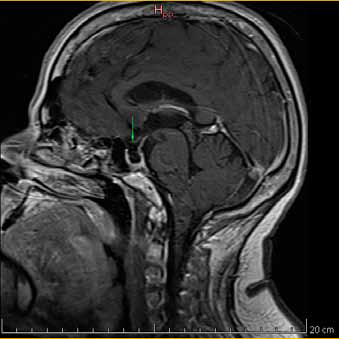

En exámenes de laboratorio se obtuvieron los siguientes resultados: IGF-1 372 ng/ml (69 - 200 ng/mL); prueba de tolerancia oral a la glucosa midiendo GH (PTG-GH): 0 minutos - 2,14/ 30 minutos - 1,38/ 60 minutos - 1,49/ 90 minutos - 1,52/ 120 minutos - 1,52/ 150 minutos - 1,55/ 180 minutos - 1,21 ng/ml; TSH: 1.28 ulU/ml (0.4 - 4 ulU/ml); prolactina: 5.2 ng/ mL (1.9 - 25 ng/mL). Los estudios de imagen informaron: RMN (Resonancia magnética nuclear) de hipófisis región selar parcialmente llena de líquido cefalorraquídeo (LCR) con dificultad para identificar el tejido hipofisario, herniación de aracnoides y el LCR que comprime a la glándula contra el suelo selar; tras la administración de contraste solo se aprecia refuerzo del infundíbulo, tallo hipofisario en línea media de aspecto normal, quiasma óptico de características normales, estructura hipotalámica normal, asimetría en la relación de los diámetros mayores entre el macizo cráneo facial y la bóveda craneal (Figura 1a y 1b). En Radiografía (Rx) columna: Rotoescoliosis, acentuación de la lordosis lumbar, disminución de espacios discales lumbares. Rx rodilla: prominencia de las espinas tibiales medial y lateral, disminución del espacio interarticular femoropatelar y femorotibial interno, osteofitos en cóndilo femoral y tibial. Rx de mano: erosiones óseas marginales, estrechamiento de los espacios interfalangicos.

Figura 1a. RMN de silla turca contrastada con gadolinio. Corte sagital en T1. Cortes 2.5 mm. Se señala región selar.

Figura 1b. RMN de silla turca contrastada con gadolinio. Corte coronal en T1. Cortes 2.5 mm.